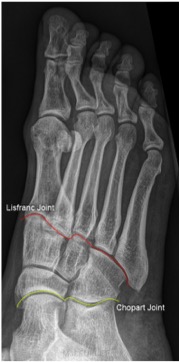

Joints

• Lisfranc

• divides forefoot + midfoot

• Chopart

• divides midfoot + hindfoot